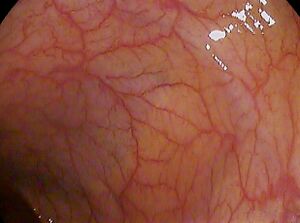

صورة من تنظير القولون للثنيات القولونية،

غشاء مخاطي طبيعي. يمكن رؤية الطحال من خلاله: الجزء الأسود.

تنظير القولون هو تنظير للأمعاء الغليظة والأجزاء البعيدة من الأمعاء الدقيقة باستخدام كاميرا اقتران الشحنة أو كاميرا ألياف بصرية على أنبوب مرن يمر عبر فتحة الشرج. يمكن لتنظير القولون أن يوفر تشخيصًا بصريًا (على سبيل المثال القرح والزوائد اللحمية) ويمنح الفرصة لأخذ خزعة أو إزالة آفات سرطان القولون والمستقيم المشتبه بها. يمكن أن يزيل تنظير القولون الزوائد اللحمية التي يصل حجمها إلى ملليمتر واحد أو أقل. بمجرد إزالة الأورام الحميدة، يمكن فحصها بمساعدة المجهر لتحديد ما إذا كانت سرطانية أم لا. يستغرق الأمر 15 عامًا أو أقل حتى تتحول السليلة إلى ورم سرطاني.